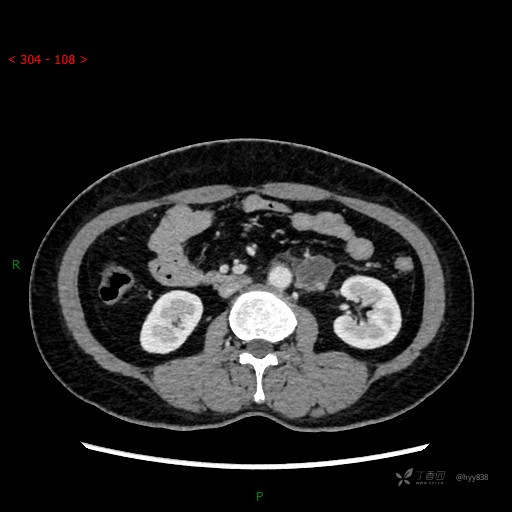

静脉期

CT平扫是外院的,因图像质量原因,不方便上传!